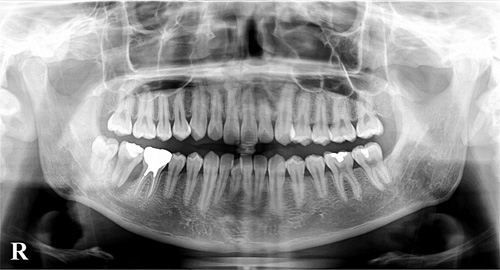

レントゲンにはお口全体を撮影するパノラマレントゲンと2~3本の歯を撮影するデンタルレントゲンがあります。

大きなサイズのパノラマレントゲンは、顎の骨の内部の病気や歯周病の進行、大まかな虫歯、親知らずの状態、歯の並びなどを確認することができます。